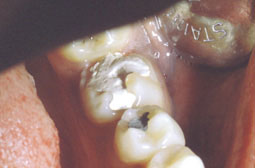

Ainsi, l’indication des amalgames collés peut s’étendre aux dents fortement délabrées par les processus carieux, soit comme traitement permanent sur dents pulpées, soit comme reconstitution provisoire dans l’attente d’une reconstitution prothétique ultérieure. En effet, le collage permet d’éviter les artifices de rétention secondaires mutilants pour l’organe dentaire, tels les vis ou les puits dentinaires.

- Dans le cas de molaires très délabrées, chez le jeune, dans l’attente de l’édification radiculaire.

- Dans le cas de dents délabrées et traitées endodontiquement. En effet, cette technique permet de différer l’étape prothétique.

Technique opératoire: (voir cas clinique)